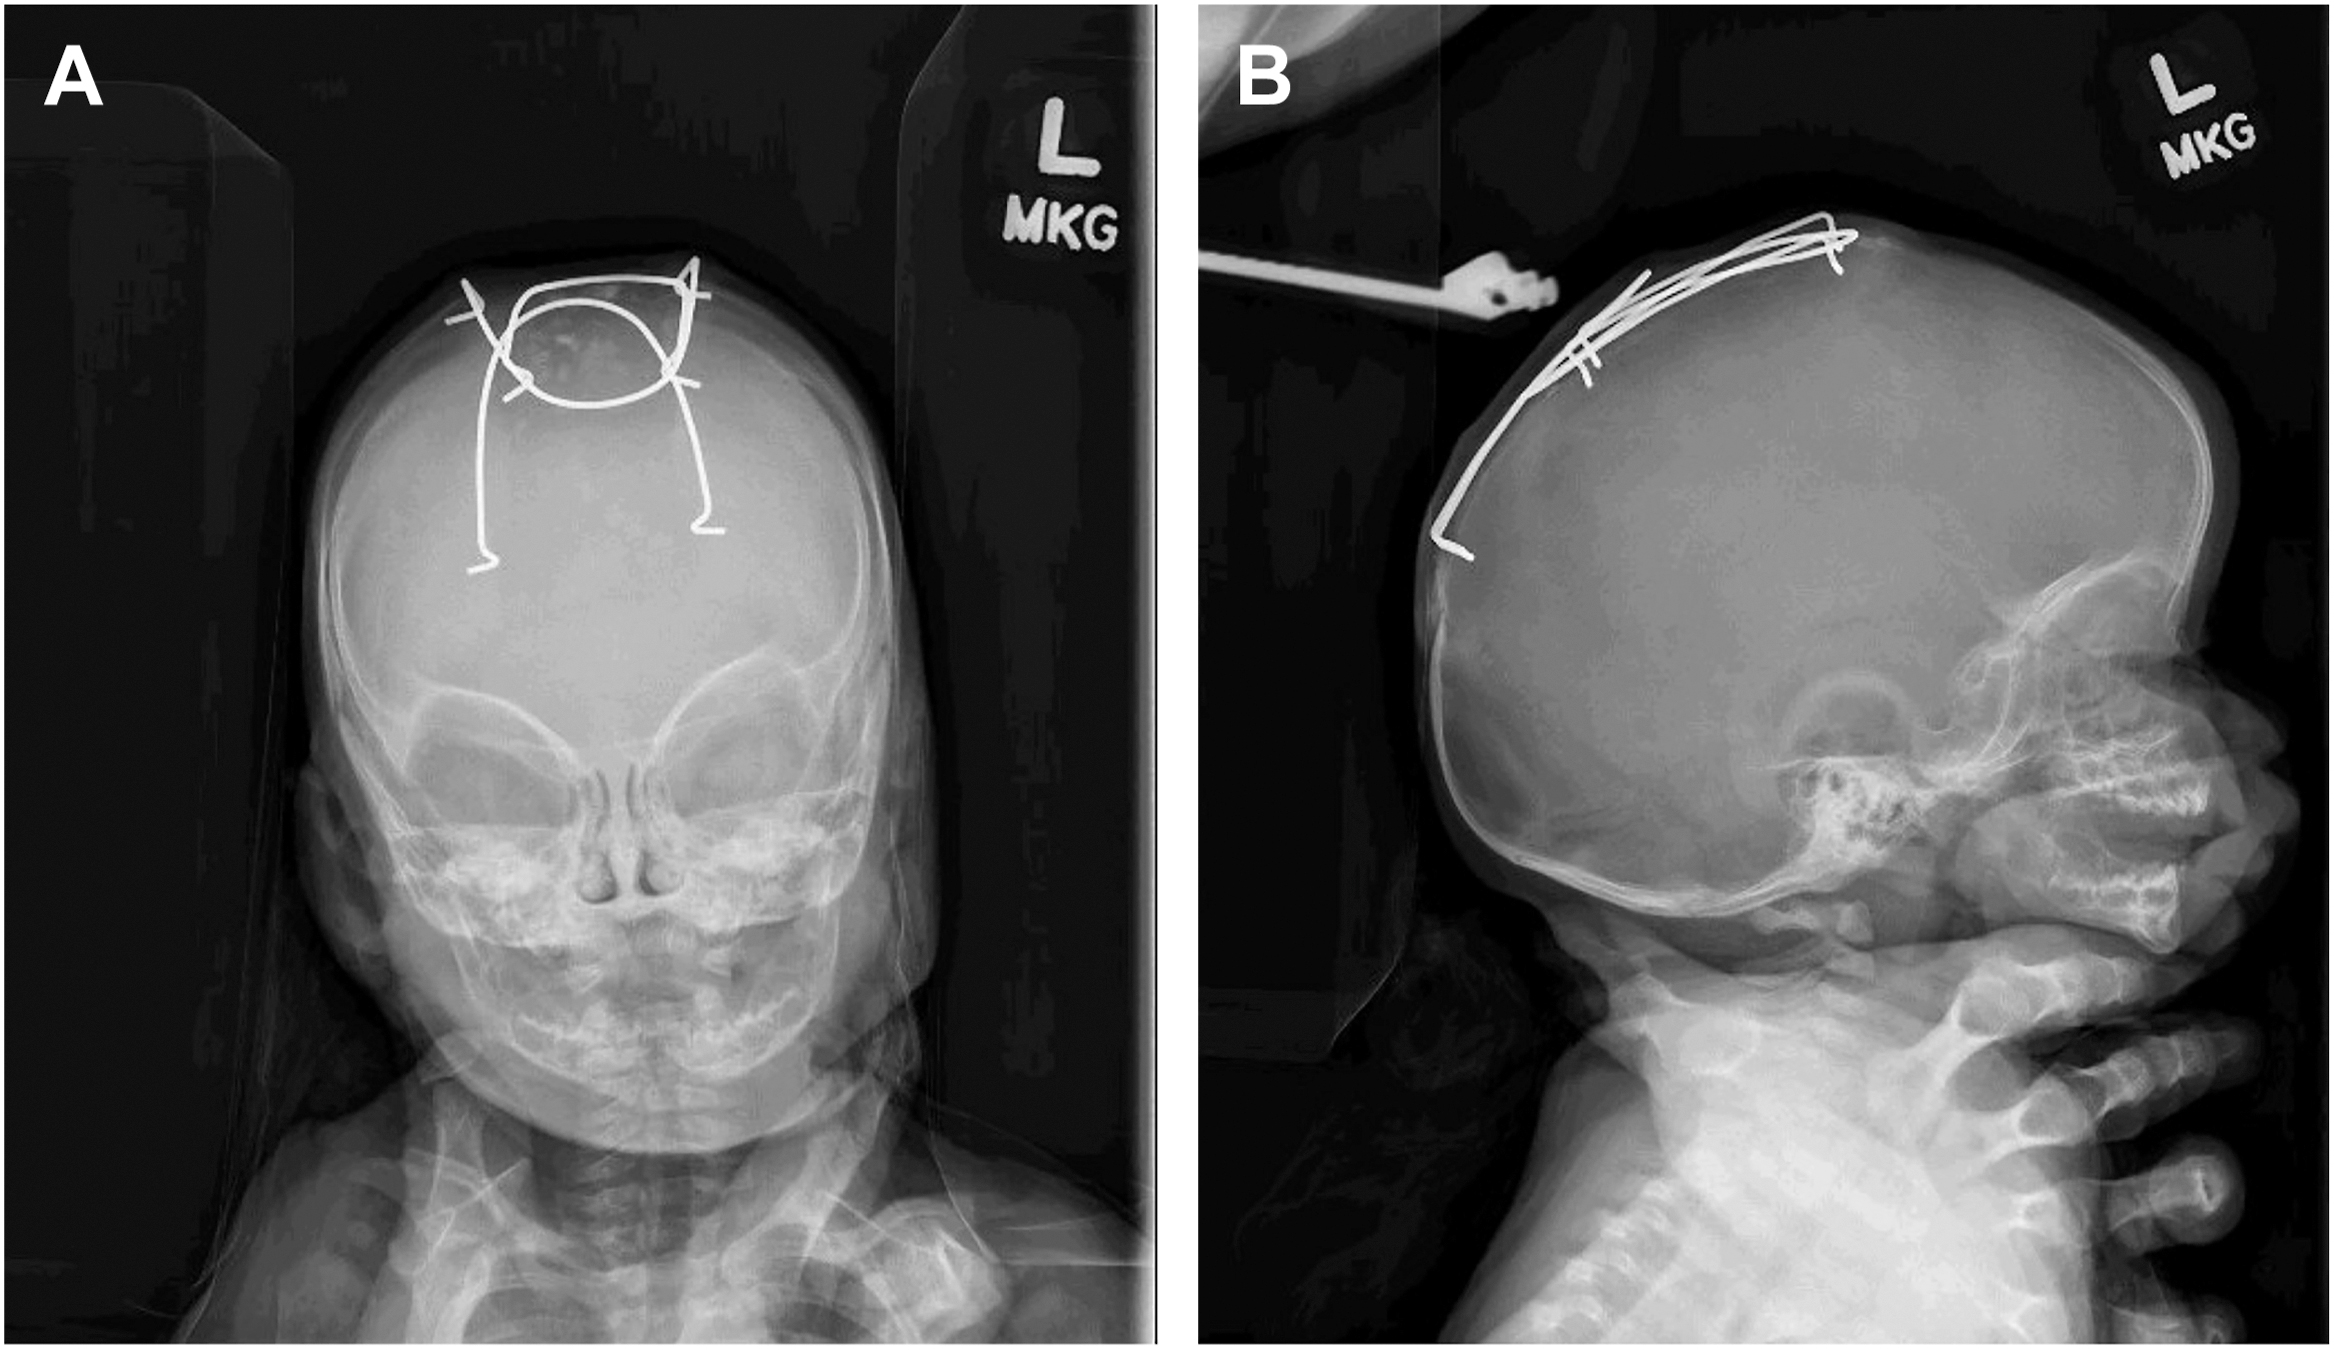

In contrast, suturectomy-based approaches involve smaller ostectomies performed at a younger age, typically through smaller incisions, and, at times, with the assistance of an endoscope. Brain growth alone is inadequate to correct cranial dysmorphology following suturectomy; a molding helmet, cranial spring, or cranial distractor is needed to facilitate reshaping. If molding orthosis is employed, the patient wears a custom-fitted helmet for 6 to 12 months to help mold the skull into a more natural shape. For spring-assisted surgery, a similar suturectomy is performed, and 2 to 3 springs are placed to gradually expand the cranial vault. These springs apply continuous outward pressure, allowing for controlled and progressive correction of the skull deformity ( Fig. 2 ). The springs are typically removed once sufficient reshaping has been achieved and the cranial defect is able to reossify after a few months.